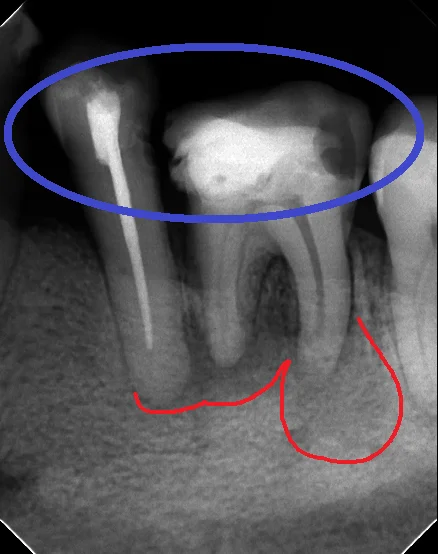

まずは術前のレントゲンです。

どちらも本来クラウン形態で治療すべきところを無理やりレジンにて治療されてしまっています。

青い部分がレジンで治療されたところなのですが・・・・一般の方が見ても、割れてしまって隙間だらけになっているのが分かるかと思います。

そしてその結果、本来は細菌が居ないハズの根管(神経の管の事です)内に細菌感染が生じて、根の先に大きく膿が溜まってしまっています。(赤い部分)

当然全く合っていない詰め物なので、食べカスは食事の度に歯に挟まり、歯周病も進んでしまっています。